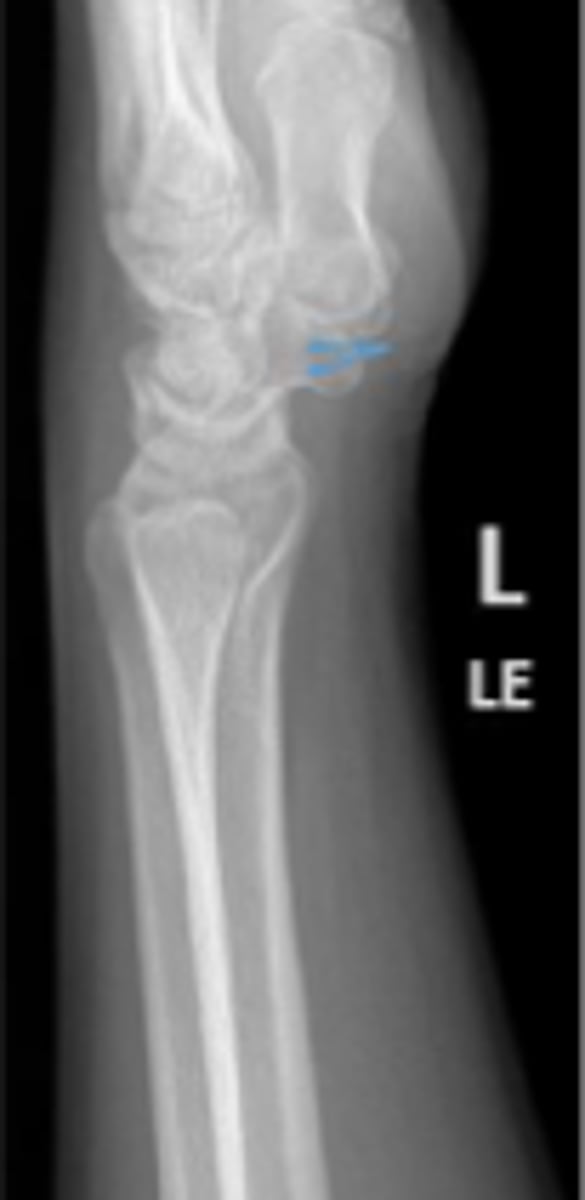

Medial oblique of the left wrist

What is the name of the radiographic view?

DRUJ

What is the arrow pointing to?

< and equal to 2mm

What is the normal measurement of this space?